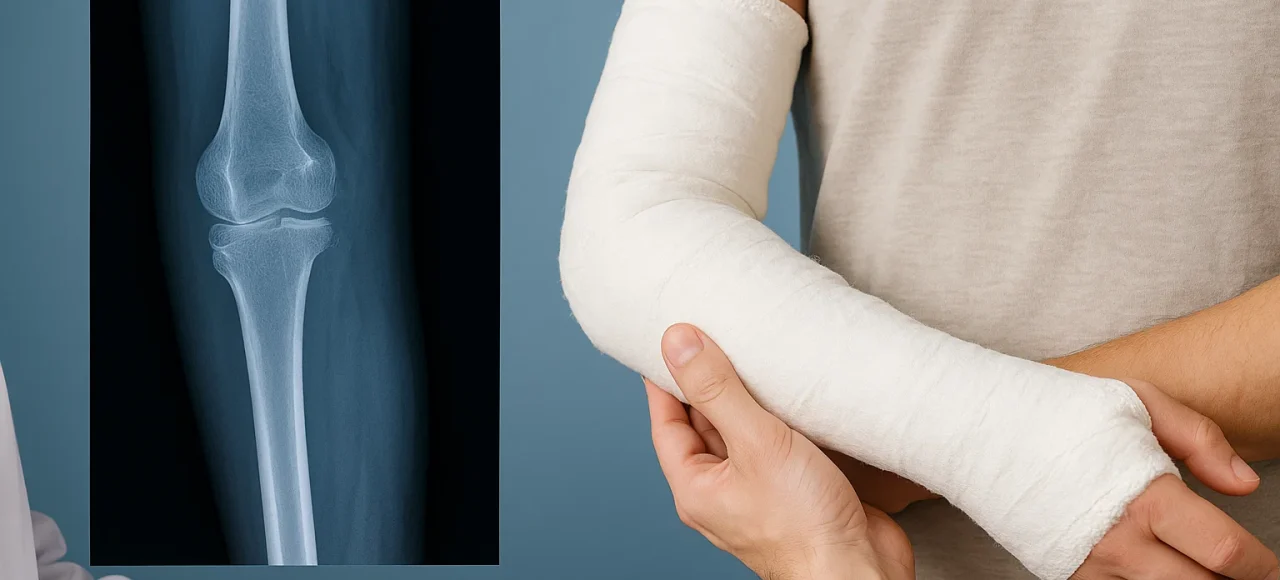

fracture du tibia

La fracture du tibia est une blessure fréquente, surtout chez les sportifs et les victimes d’accidents de la route. Cette fracture peut varier en gravité, allant d’une simple fissure à une fracture complète nécessitant une intervention chirurgicale. Comprendre les options de traitement disponibles est essentiel...